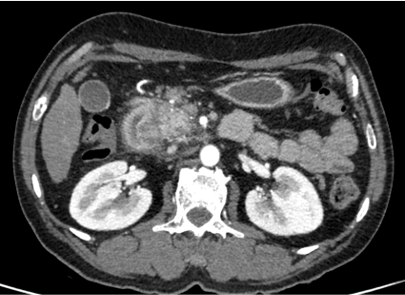

48 year old male Presented with history of 3 episodes of melena. No known comorbidities Gastro -Duodenoscopy - Erosive duodenitis Colonoscopy – unremarkable.

48 year old male Presented with history of 3 episodes of melena. No known comorbidities Gastro -Duodenoscopy -Erosive duodenitis Colonoscopy – unremarkable.